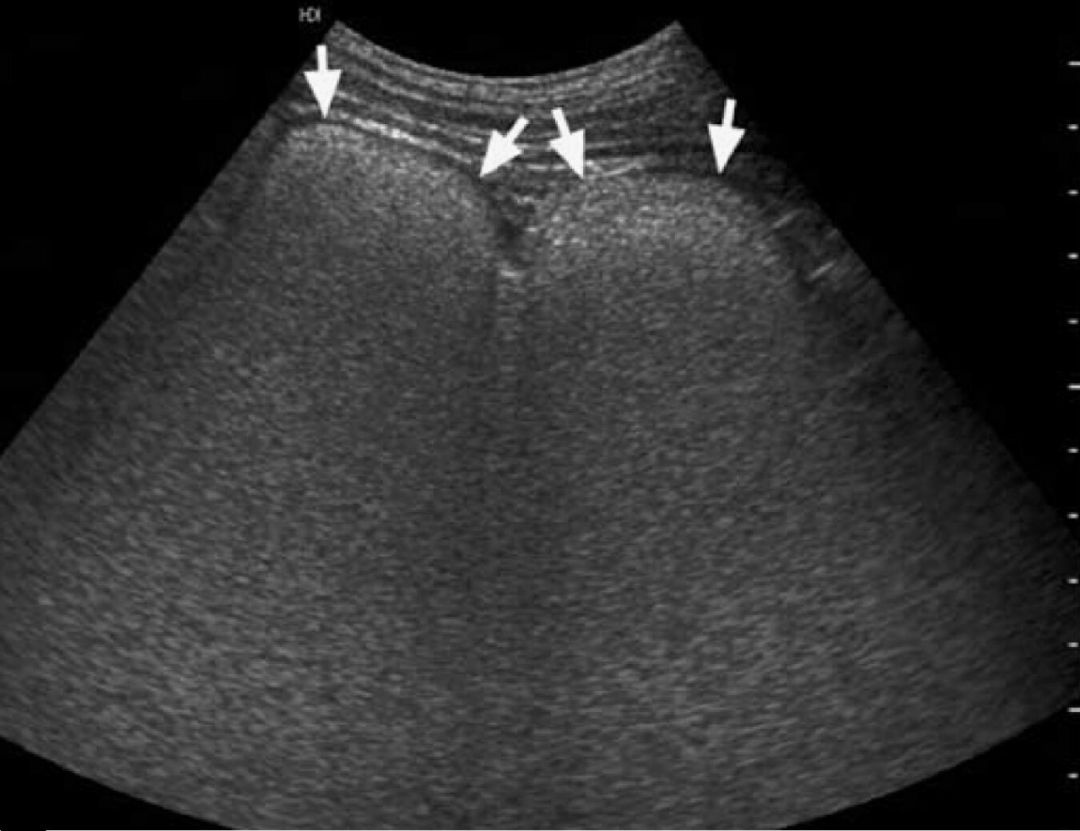

图8-9:肿瘤转移所致“白肠”。病例4,患者,女性,63岁,结肠癌广泛腹膜转移,恶病质。超声显示肠壁黏膜层呈节段性“白肠”高回声增厚(△所示),而黏膜下层则因水肿而呈低回声带,两者对比鲜明;此外,“白肠”周边可见腹腔积液和高回声增厚的肠系膜(箭头所示)。Hint:这种不规则“白肠”与肿瘤晚期肠壁受累(淋巴管阻塞、间质水肿和蛋白丢失等)所致复杂病理生理变化有关。